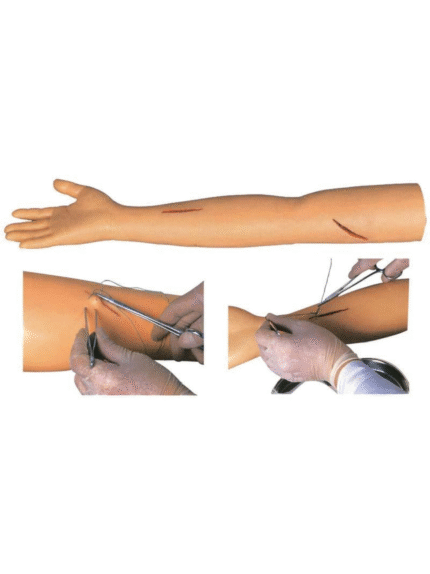

ATL-104 ADVANCED SUTURE PRATICE LEG SOFT

ATL-105 ADVANCED SUTURE PRACTICE ARM SOFT